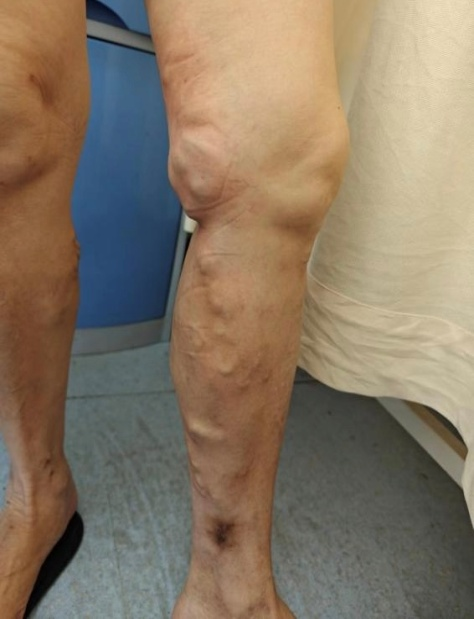

想象一下,我們的血管就像一條條河流,負責把血液從腳送回心臟。但有時候,這些“河流”會變得蜿蜒曲折,甚至在某些地方變得膨脹,導致血液在腿部滯留。這就像是排水管被堵住了,水流積起來排不出去,我們腿部那些外觀類似于蚯蚓的血管,就是靜脈曲張。

曲張的血管:腿部的血管顏色看起來很顯眼,彎彎曲曲,就像“蚯蚓”一樣。